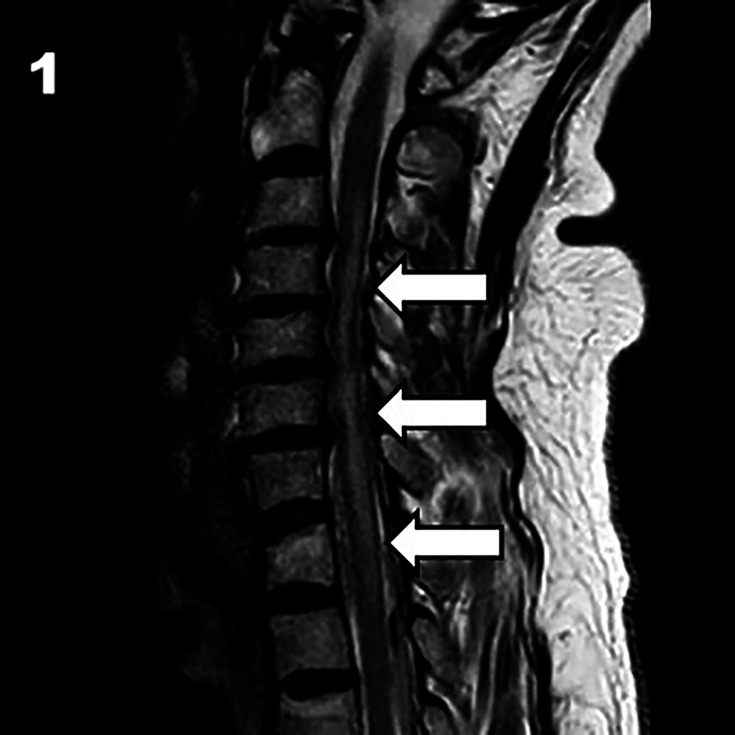

背景:脊髓梗死(SCI)与不良临床预后相关。静脉溶栓(IVT)是一种公认的治疗缺血性脑卒中的方法。然而,其在脊髓损伤中的疗效尚不清楚。目的:我们报告一例急性脊髓缺血溶栓治疗后明显改善的病例,并回顾目前的文献,探讨这种治疗的安全性和可行性。方法:我们回顾了脊髓损伤行静脉注射治疗的文献。我们回顾了他们的病史、临床表现和报告的结果。结果:除了我们的病例,我们的回顾包括19例脊髓损伤的IVT治疗。平均年龄62.87±15.27岁,女性占36%。大多数病例为自发性,并在发病后240分钟内得到治疗。89%的病例取得了良好的结果,包括在延长的时间窗口内治疗的少数病例。两例均无因出血引起的临床恶化。结论:在某些情况下,在适当的检查后,IVT可能被认为是脊髓损伤的治疗方法。大多数病例取得了良好的结果,没有一例因溶栓后出血而出现临床恶化。该方法的安全性和有效性有待进一步研究。

Background: Spinal cord infarction (SCI) is associated with poor clinical outcome. Intravenous thrombolysis (IVT) is a well-established treatment for cerebral ischaemic stroke. However, its efficacy in SCI is unknown.

Objective: We present a case of acute spinal cord ischaemia with significant improvement following thrombolysis and review the current literature to explore the safety and feasibility of this treatment.